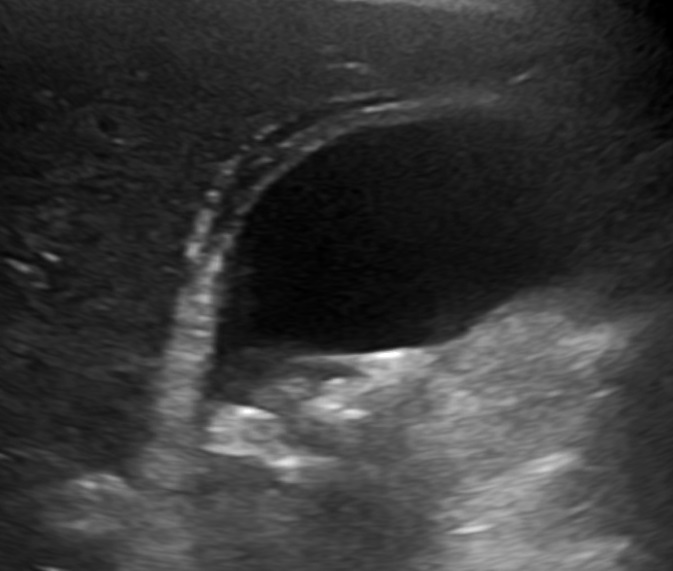

Gallstones

Gallstones are also called cholelithiasis.

The gallbladder contains solid, rounded stones because of precipitation of cholesterol (cholesterol stones) or bilirubin (bilirubin stones) in bile.

Cholesterol stones (yellow) are the most prevalent type (ninety percent), particularly in the West.

Gallstones are typically radiolucent (10 percent of gallstones are radiopaque because of associated calcium).